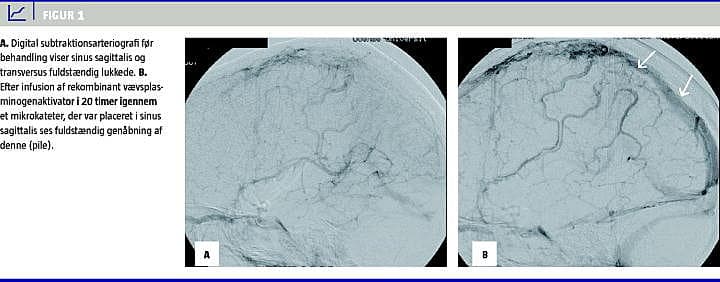

På trods af denne behandling blev patienten i løbet af de næste to døgn tiltagende bevidsthedssvækket, afatisk og fik tiltagende højresidig hemiparese. Hun blev herefter overflyttet til Odense Universitetshospital, hvor hun fortsat udviklede faldende bevidsthedsniveau med fald i GCS til 10. Det blev herefter besluttet at foretage intravaskulær trombektomi. Arteriografi viser lukning af sinus sagittalis og venstre sinus transversus (Figur 1A ). Via vena femoralis blev der oplagt 6F-guidekateter, som blev ført op gennem vena jugularis og op i sinus sigmoideus. Herigennem blev et mikrokateter ført op i sinus sagittalis, hvor det var muligt at føre det frem til sutura coronalis. Der blev forsøgt mekanisk trombolyse uden resultat.

Herefter blev mikrokateteret placeret i tromben, og der blev infunderet rt-PA 1 mg/time i 20 timer. Kontrolarteriografi viste åbenstående sinus sagittalis og begyndende passage gennem sinus transversus (Figur 1B). Patienten blev ekstuberet og tilbageflyttet til den regionale neurologiske afdeling to dage senere i klar bedring med normalt bevidsthedsniveau. Hun blev udskrevet efter 28 dage motorisk restitueret, men med lettere kognitive sequelae.